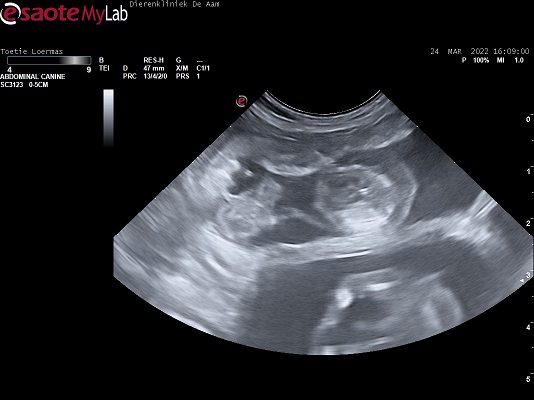

Hieronder ziet u twee echo's van puppen in de baarmoeder van Cappucino!